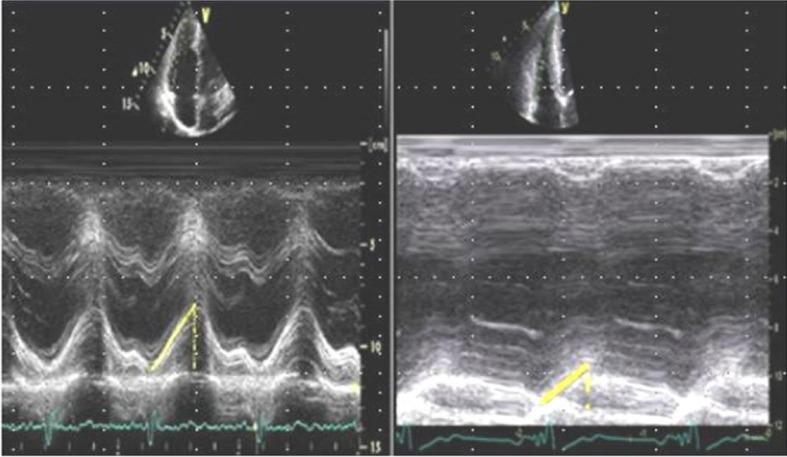

Thirty-seven children (boy:girl=21:16; mean age, 9.52±2.20 years), who underwent T&A forsleep apnea due to ATH, were included. We analyzedthe mean pulmonary artery pressure (mPAP), the presence and the maximal velocity of tricuspid regurgitation (TR), the tricuspid annular plane systolic excursion (TAPSE), and the right ventricular myocardial performance index (RVMPI) with tissue Doppler echocardiography (TDE) by transthoracic echocardiography pre- and post-T&A. The follow-up period was 1.78±0.27 years.

Only the RVMPI using TDE improved after T&A (42.18±2.03 vs. 40±1.86, P=0.001). The absolute value of TAPSE increased (21.45±0.90 mm vs. 22.30±1.10 mm, P=0.001) but there was no change in the z score of TAPSE pre- and post-T&A (1.19±0.34 vs. 1.24±0.30, P=0.194). The mPAP was within normal range in children with ATH, and there was no significant difference between pre- and post-T&A (19.6±3.40 vs. 18.7±2.68, P=0.052). There was no difference in the presence and the maximal velocity of TR (P=0.058).

纳入37例行T&A治疗因ATH导致的睡眠呼吸暂停的儿童(男∶女 = 21∶16;平均年龄9.52±2.20岁)。我们通过经胸超声心动图,采用组织多普勒超声心动图(TDE)在T&A前后分析平均肺动脉压(mPAP)、三尖瓣反流(TR)的存在情况及最大流速、三尖瓣环平面收缩期位移(TAPSE)和右心室心肌做功指数(RVMPI)。随访期为1.78±0.27年。

仅采用TDE的RVMPI在T&A后有所改善(42.18±2.03对40±1.86,P = 0.001)。TAPSE的绝对值增加(21.45±0.90 mm对22.30±1.10 mm,P = 0.001),但T&A前后TAPSE的z值无变化(1.19±0.34对1.24±0.30,P = 0.194)。ATH儿童的mPAP在正常范围内,T&A前后无显著差异(19.6±3.40对18.7±2.68,P = 0.052)。TR的存在情况及最大流速无差异(P = 0.058)。